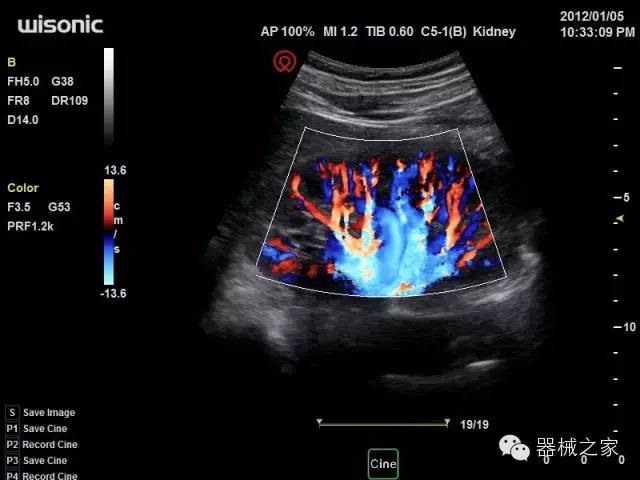

臨床圖片賞析

·全球目前唯一一款配備主機雙探頭接口,整機重量(含電池)在5公斤以內(nèi)的便攜式彩超;

·獨有的HoloTM PW 實時3取樣門PW成像技術(shù),精確進行血管診斷;